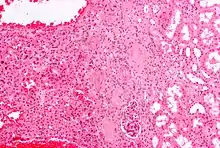

Micrograph of a renal oncocytoma. H&E stain.

An oncocytoma is an epithelial tumor composed of oncocytes, large eosinophilic cells having small, round, benign-appearing nuclei with large nucleoli.

An oncocytoma is a tumor made up of oncocytes, epithelial cells characterized by an excessive amount of mitochondria, resulting in an abundant acidophilic, granular cytoplasm.[1][2] The cells and the tumor that they compose are often benign but sometimes may be premalignant or malignant.